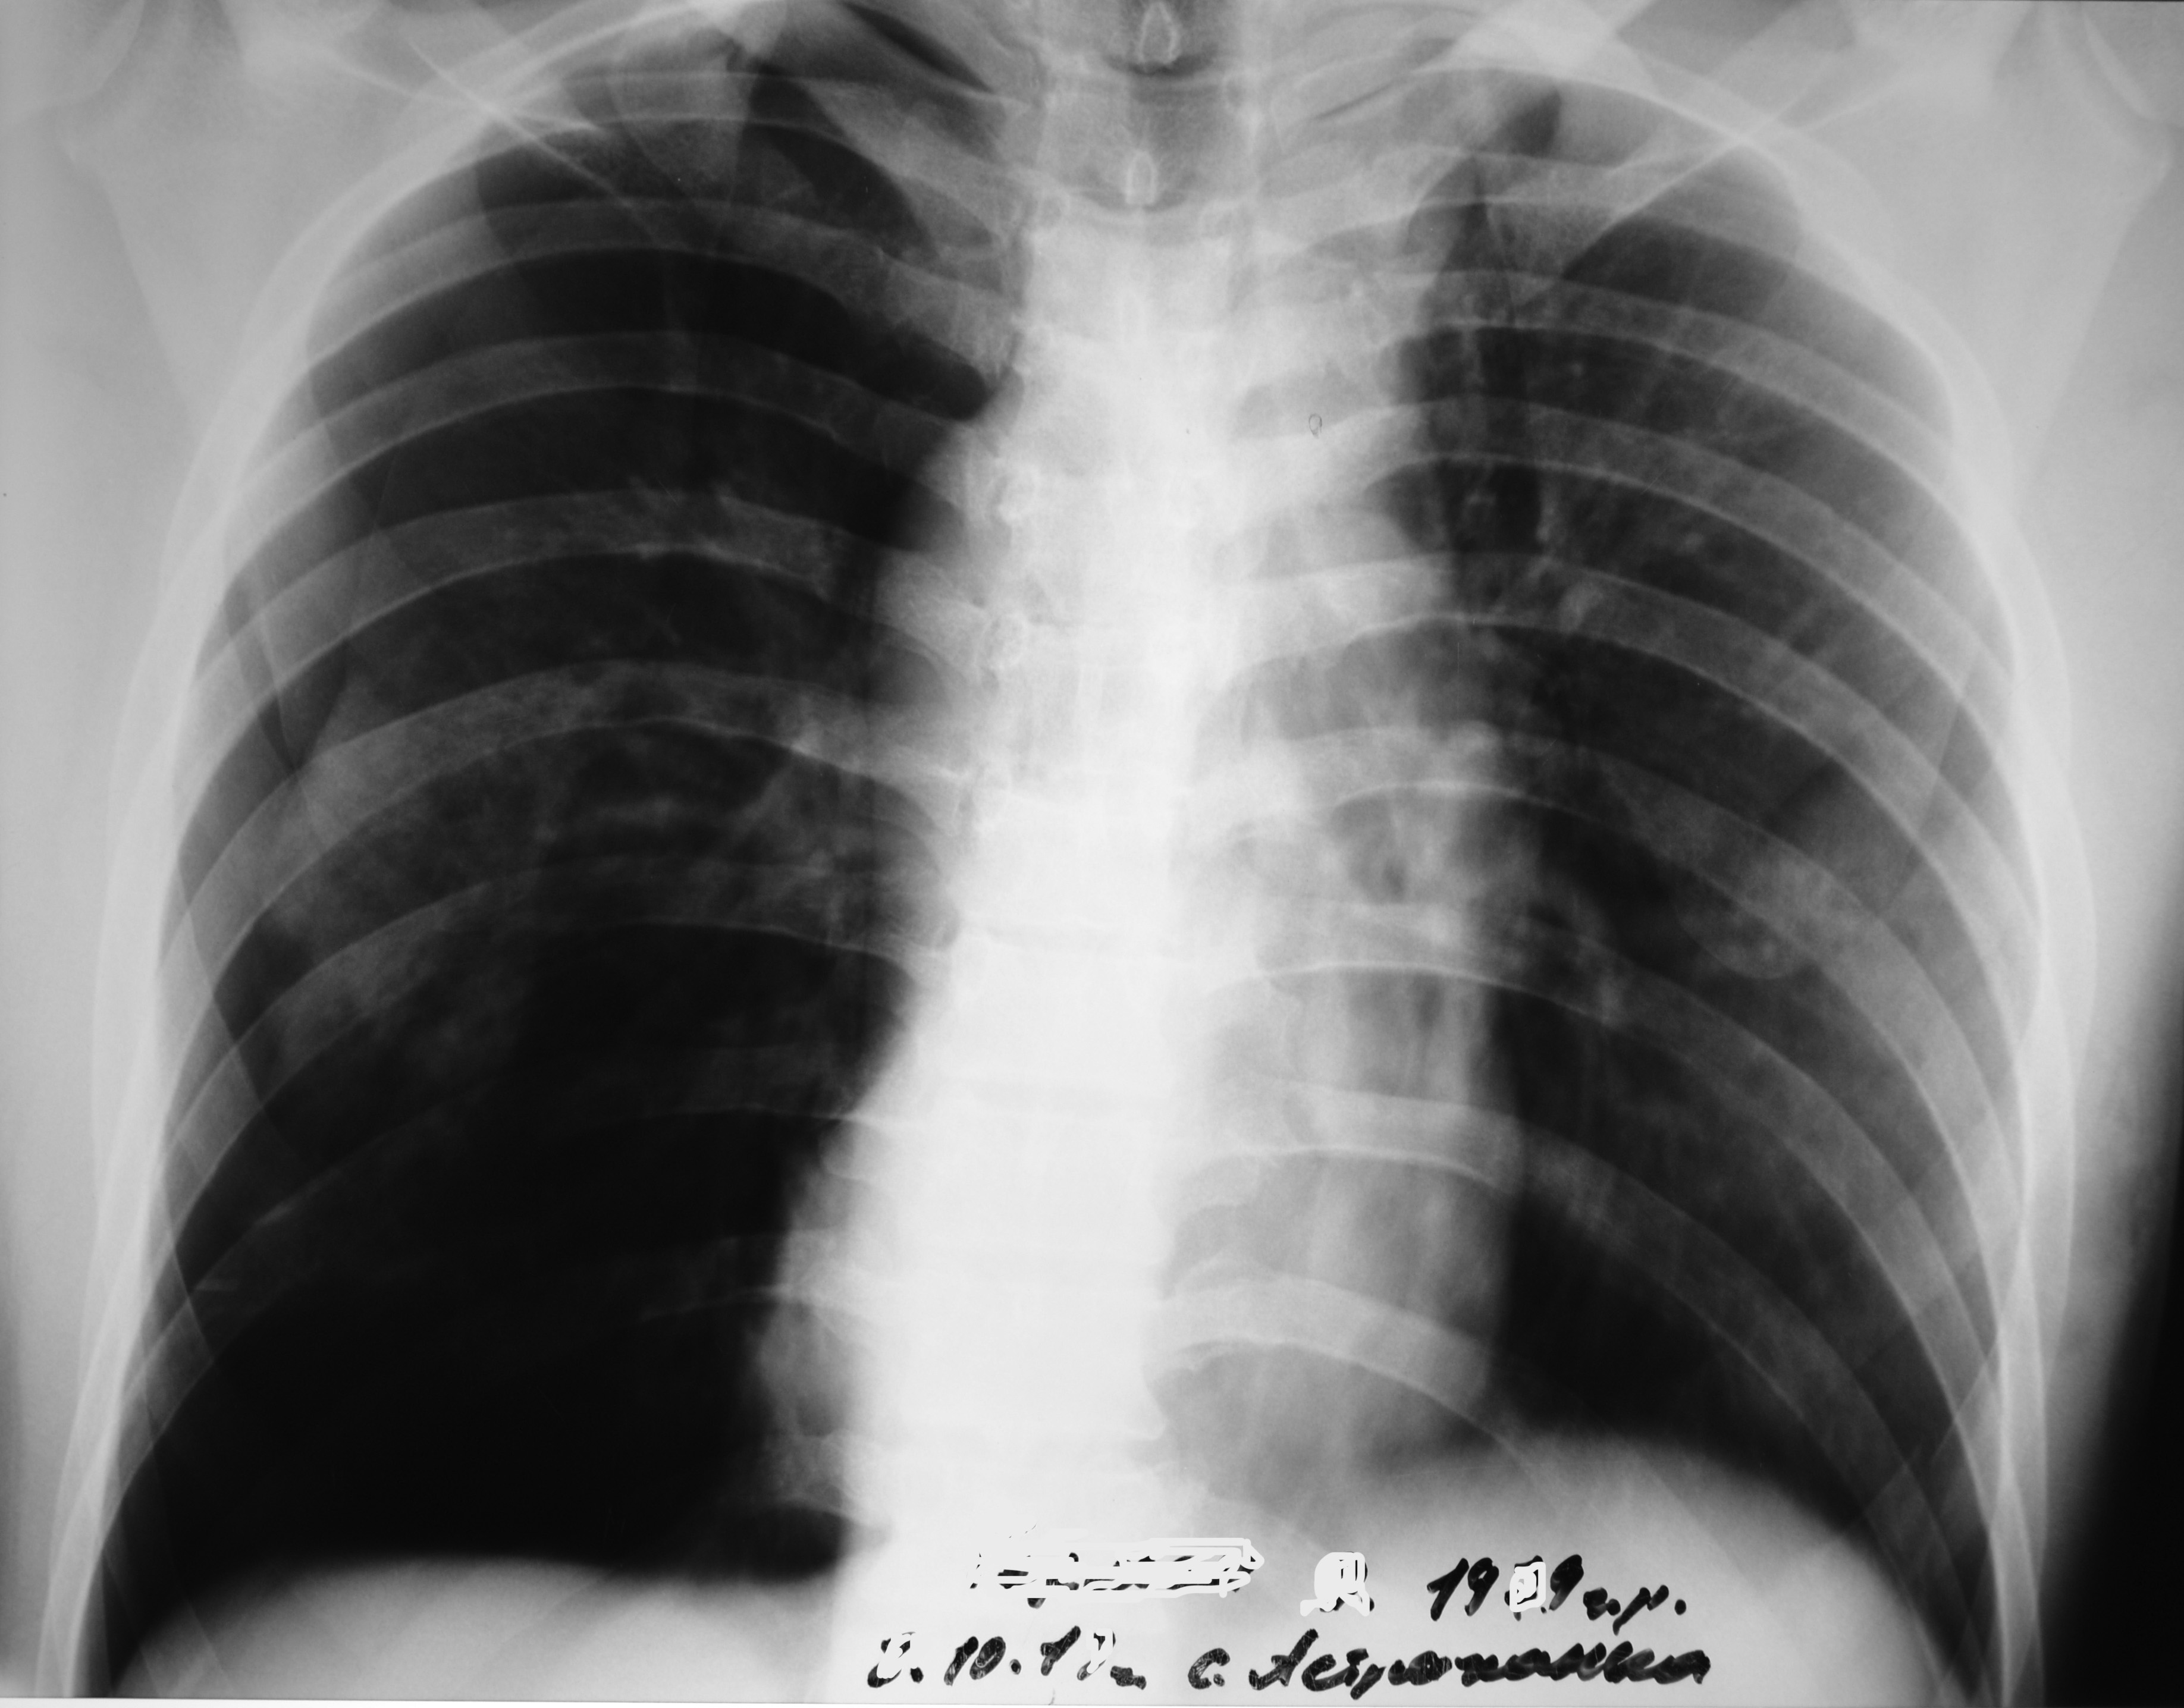

Обзорная рентгенограмма грудной клетки в передней проекции: перелом тел VII-VIII ребер слева. Хронический бронхит, викарная эмфизема верхних долей легких. Гипертрофия правого сердца.

 параклинических методов исследования: сахар крови – 8,0 ммоль/л; обзорная рентгенограмма грудной клетки в передней проекции: перелом тел VII-VIII ребер слева. Хронический бронхит, викарная эмфизема верхних долей легких. Гипертрофия правого сердца –